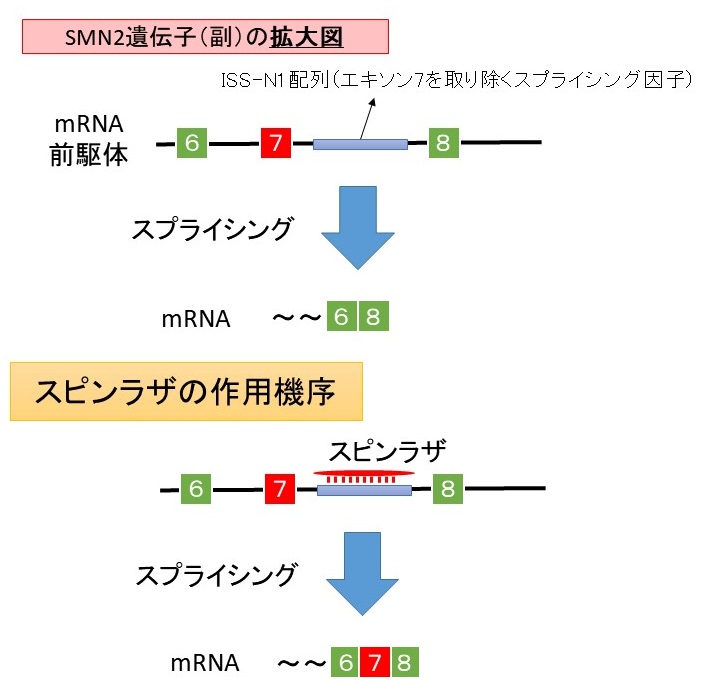

全脊椎の作用と性質

全脊椎の作用と性質